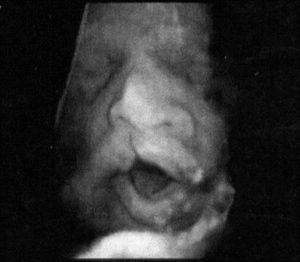

Адекватная диагностика расщепления неба или губы не представляет большой трудности. Как уже отмечалось, диагноз «волчья пасть» и «заячья губа» становятся очевидными на УЗИ в 1 – 2 триместрах беременности.

Распознать признаки заячьей губы можно еще во внутриутробном периоде. Сделать это можно при помощи УЗИ уже на 14 неделе беременности. Однако, чтобы окончательно подтвердить диагноз, потребуется собрать врачебный консилиум.

Выявляют болезнь волчья пасть ближе к концу второго триместра беременности. Однако ультразвуковое исследование не всегда информативно. Ребенок может закрыть лицо руками, либо его положение в матке не позволяет врачу провести подробный осмотр. Поэтому при возникновении сомнений рекомендуют повторное УЗИ с использованием допплера.